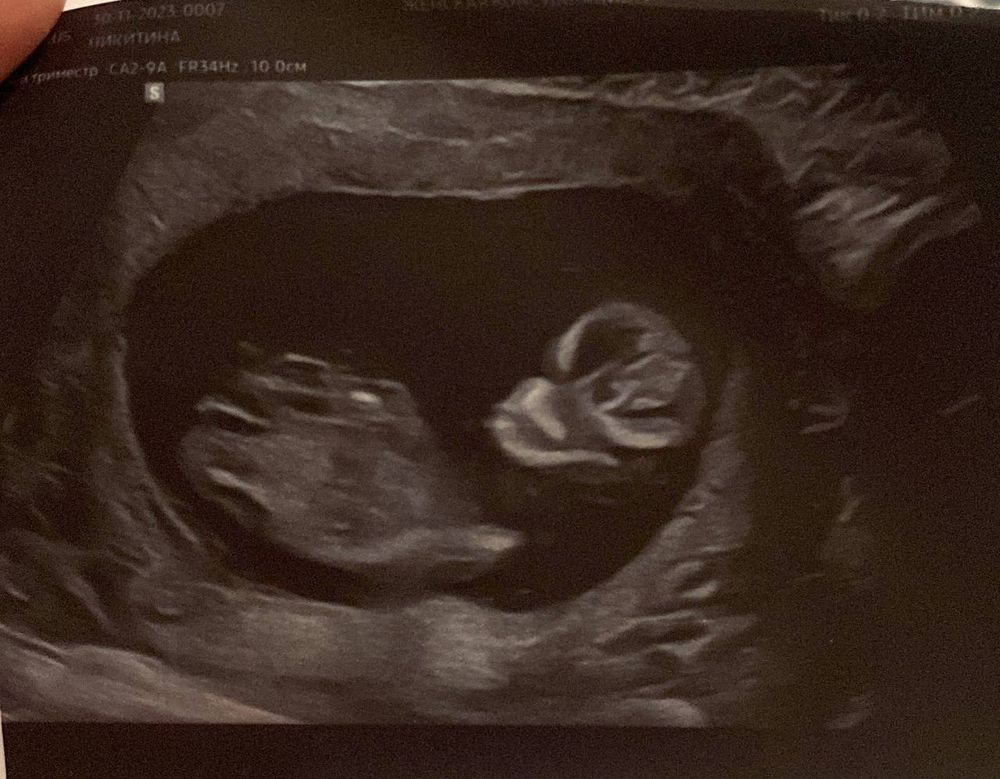

Узи первого триместра форум

Узи первого триместра форум 117 фото